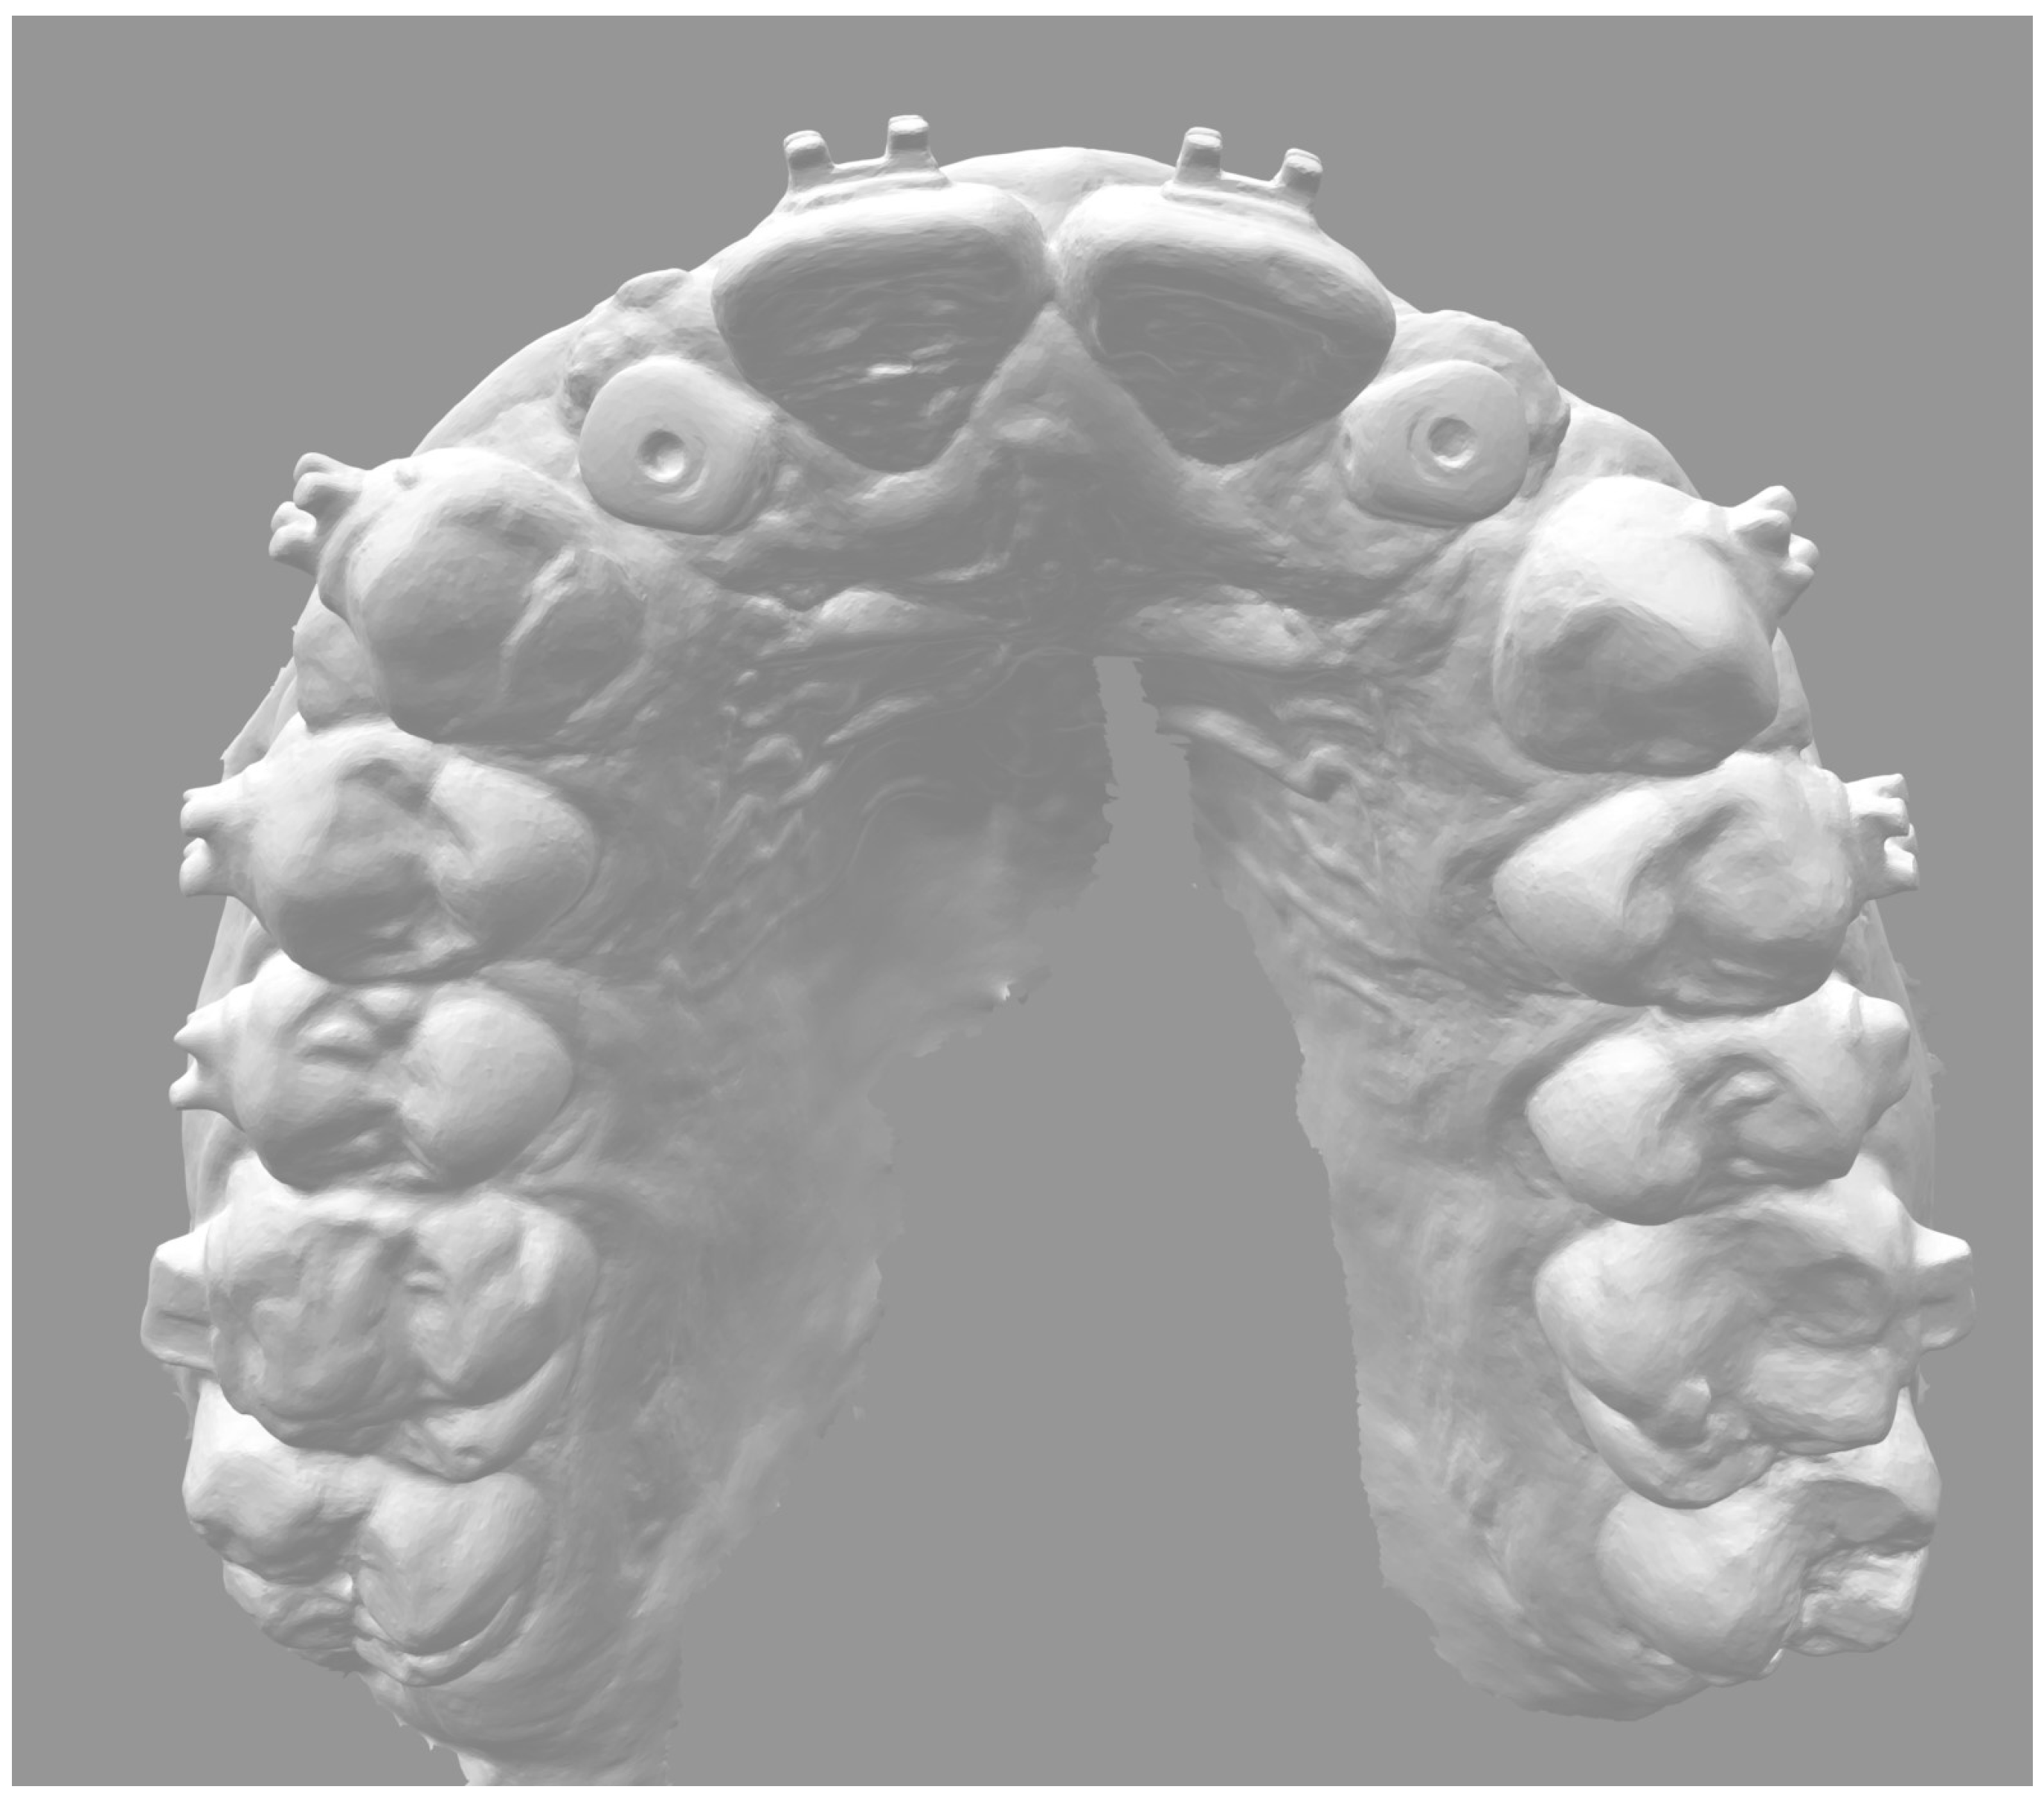

2. Materials and Methods

- 4–10 months: periodontal and orthodontic preparation (if necessary) and implant surgery;